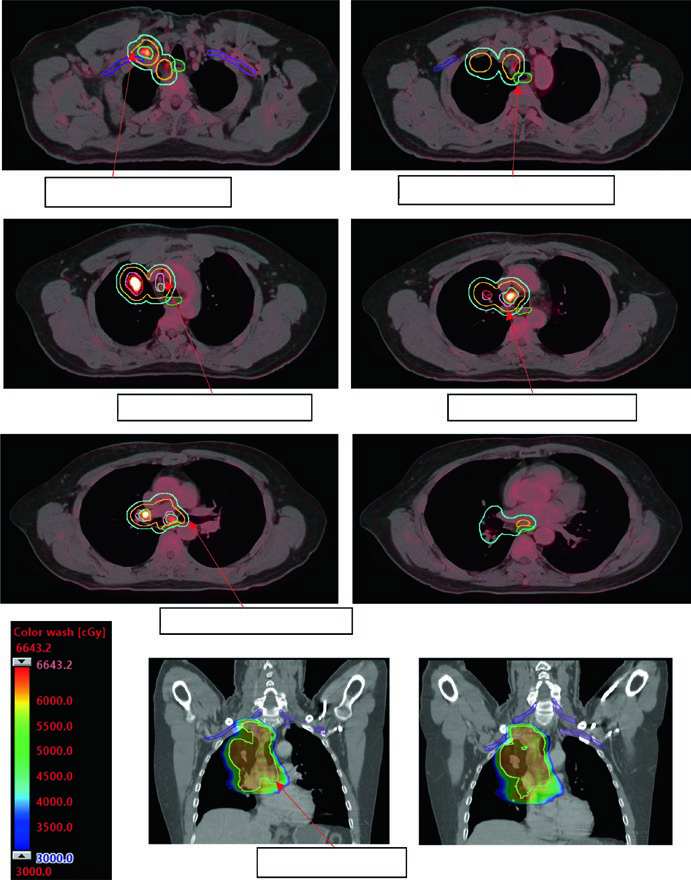

A dose máxima em ponto da PBT é restrita a 55 Gy em qualquer esquema. A Figura 13.2 do texto mostra três casos de estádio inicial: tumor periférico clássico tratado com 54 Gy/3fx, tumor próximo à PBT com 48 Gy/4fx e tumor central com 50 Gy/5fx.

A Figura 13.3 do texto ilustra um caso cT1cN3M0 IIIB: tumor no LSD com linfonodo hilar direito, subcarinal, paratraqueal e SCV direita acometidos. O plano de 60 Gy/30fx cobre todos os sítios PET-positivos com exclusão das cadeias eletivas contralaterais. A Figura 13.4 mostra um caso cT4N3M0 IIIC com SCV bilateral comprometida e síndrome de veia cava superior, exigindo campo que inclui mediastino superior bilateral.

A Figura 13.5 do capítulo mostra um tumor de 5,8 cm no LSE com positividade nos níveis 5 e 10L. O campo limitado conforme Lung ART é o utilizado, com 54 Gy/30fx.

A Figura 13.6 mostra um caso cT2N2 de estádio limitado com o campo envolvido cobrindo tumor primário e linfonodos mediastinais comprometidos, mas excluindo cadeias eletivas. O esquema utilizado foi 45 Gy/30fx BID.

O replanejamento adaptativo deve ser considerado quando a CBCT mostra mudança anatômica significativa — expansão pulmonar ipsilateral, redução de derrame ou colapso em resolução. O caso da Figura 13.7 ilustra uma lesão metastática tratada com 45 Gy/15fx: a reaer ação pulmonar durante o tratamento exigiu replanejamento para proteger o pulmão recém-arejado.